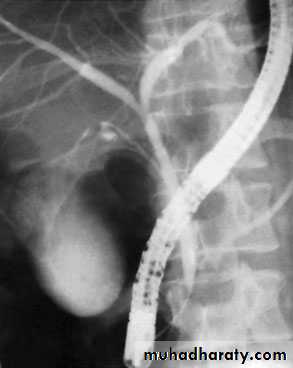

NORMAL ERCP

65Endoscopic retrograde cholangiopancreatographydemonstrating stone obstructing the common bile duct (arrow